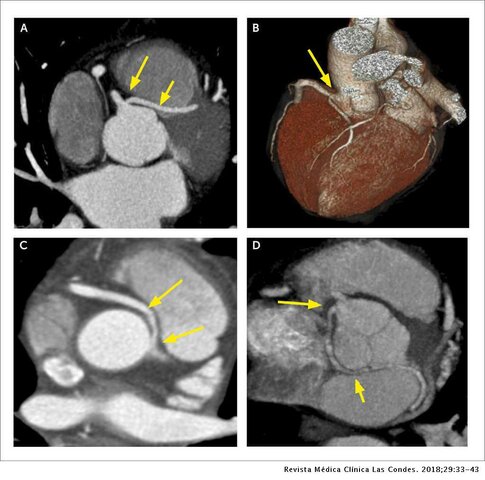

• Tomografía por rayo de electrones EBCT

Tomografía por rayo de electrones EBCT

la tomografía por rayo de electrones EBCT (del inglés Electron Beam CT), que constituye la quinta generación. El EBCT utiliza una arquitectura estacionaria (sin rotación), donde un rayo de electrones hace un barrido a lo largo de cuatro placas semicirculares que rodean al paciente. La mayor innovación de este escáner fue su alta resolución temporal (33 ms a 100 ms), suficiente para tomar imágenes del corazón.